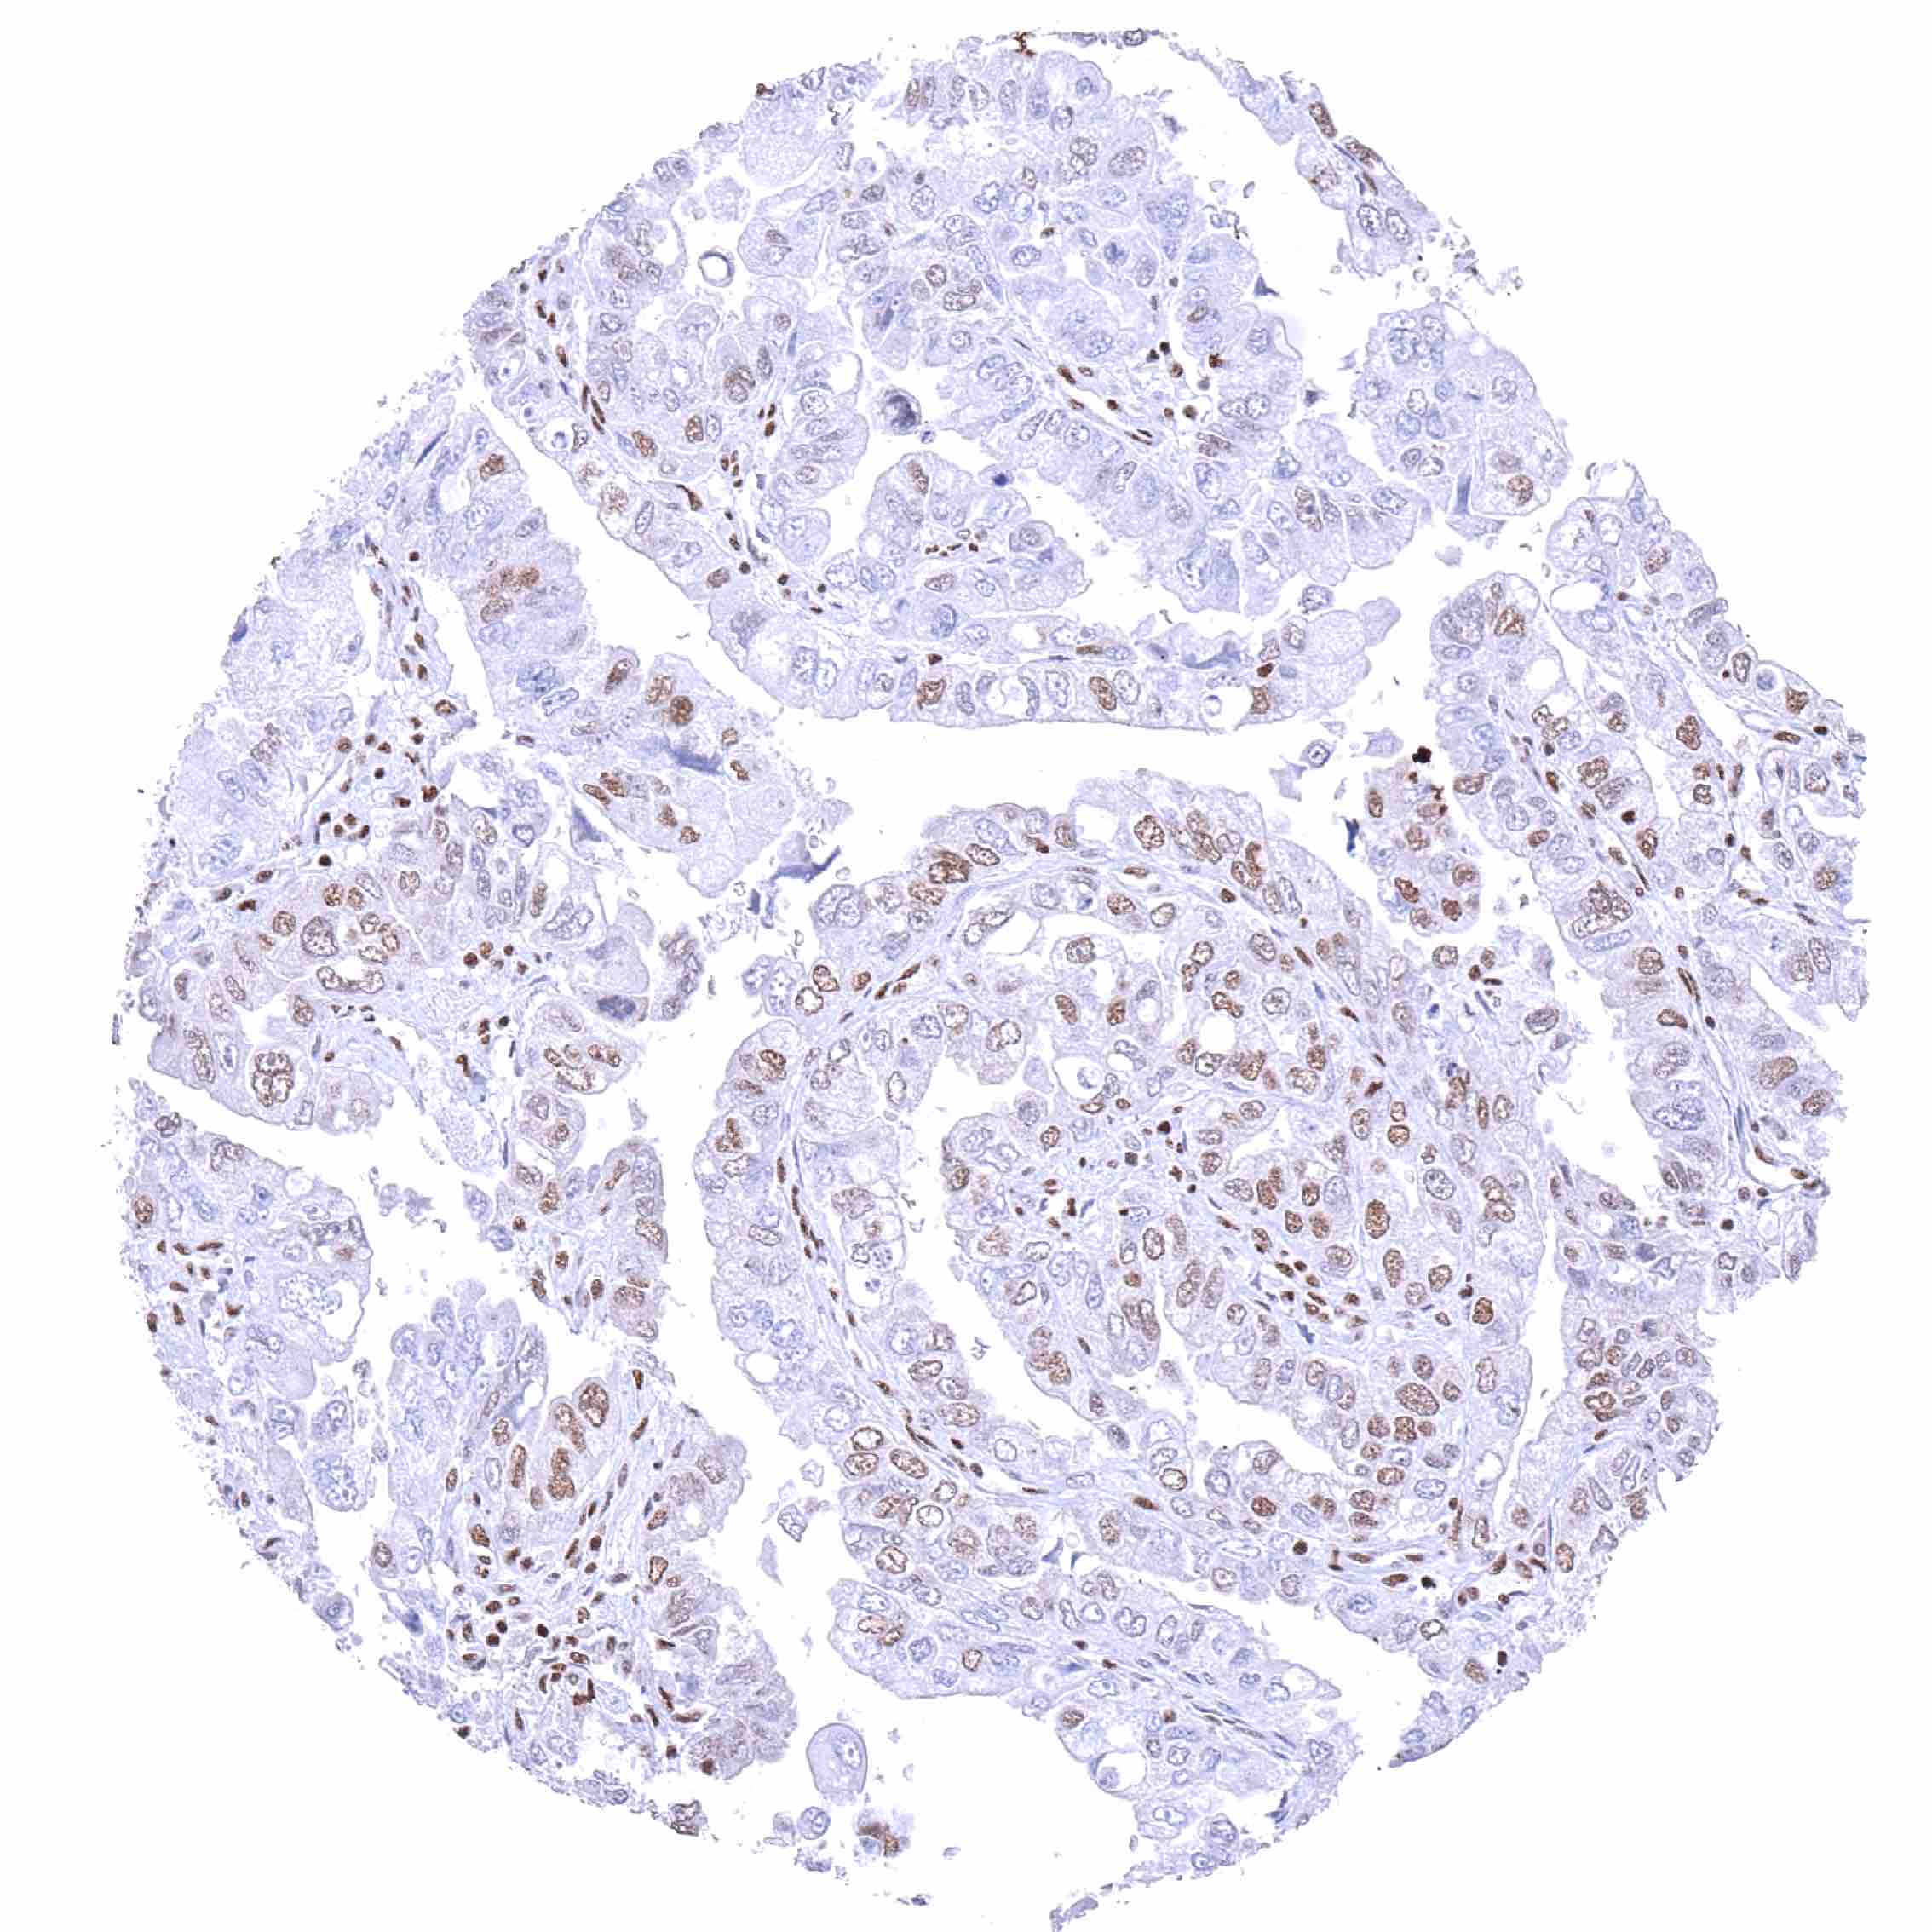

Lung – Adenocarcinoma with high level BRD4 staining of tumor cells.